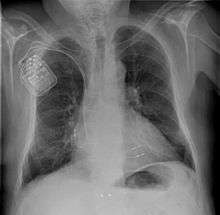

CCM devices are similar in structure to other implantable devices used for electrical stimulation of the heart, such as pacemakers or implantable cardioverter defibrillators (ICDs).[16] The currently available CCM system (as of February 2015) consists of four components, as described below.[16]

- Implantable Pulse Generator (IPG): The pulse generator generates the CCM’s non-excitatory electrical signals. The IPGs currently in use are similar in dimension to a matchbox, but have a slightly larger surface and are a little more slender (approx. 6.5 cm x 4.7 cm x 1.2 cm or approx. 2 9/16" x 1 7/8" x 1/2"). The IPG is usually implanted in the chest subcutaneously (under the skin), below the right clavicle of the patient. In some cases, the IPG remains noticeable as a slight bulge under the skin. Pulse generators combining CCM therapy with the functionality of other electrical stimulation devices such as pacemakers or ICDs are not currently available, although the development of such a combined device has already been suggested in literature.[13]

First, the doctor checks the function of the pulse generator and the leads, before positioning the leads in the heart. The positioning of the leads is verified by X-ray imaging and by the measurement of voltage and electric current through the leads (lead impedance).[16]

Following successful positioning, the leads are connected to the pulse generator. A pocket is formed under the skin or chest muscle below the clavicle of the patient in order to implant the pulse generator. The IPG is inserted in the pocket and its function is tested. If the patient happens to have a pacemaker or implantable cardioverter defibrillator, the doctor and/or a trained technician ensures that there is no interference between the two devices by performing a “crosstalk check”. Finally, the pocket is sutured and the wound is bandaged.